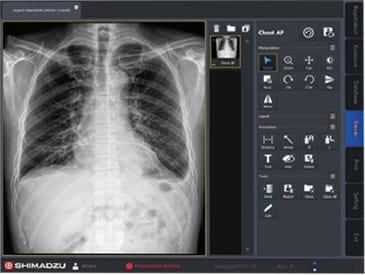

X-ray Images Display on the Second Monitor

The captured image is shown on the second monitor after exposure. Possible to confirm the image for the verification of positioning.